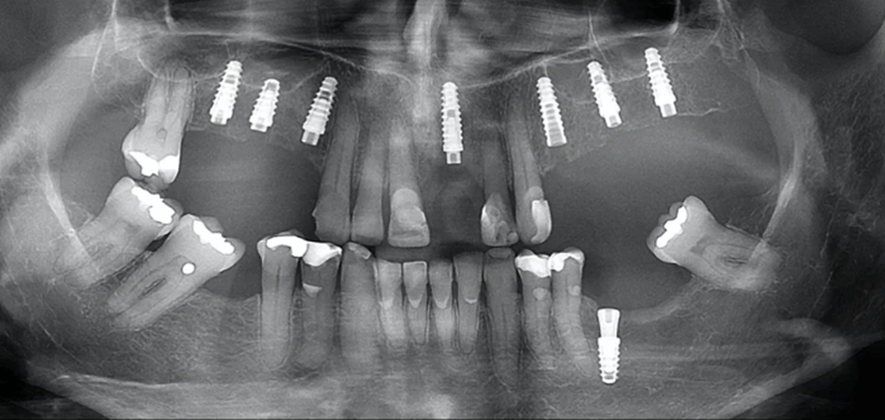

Embora muitos profissionais considerem arriscado colocar os implantes Cone Morse muito dentro do osso, eu acredito que um mergulho mais profundo destes implantes Cone Morse aumenta a previsibilidade do conjunto implante/prótese, favorecendo a saúde e estética peri-implantar. As figuras 5 e 6 ilustram um caso deste estilo.

Obviamente que mais pesquisas são necessárias para que possamos estabelecer um consenso sobre o quanto podemos colocar um implante Cone Morse dentro do osso. Contudo, devemos procurar respeitar as distâncias biológicas entre dentes e implantes e entre implantes. Assim como na dentição natural, os implantes também exigem um espaço livre de osso, a fim de que os tecidos moles possam se adaptar e este espaço parece estar nos pilares mais estreitos e longos.